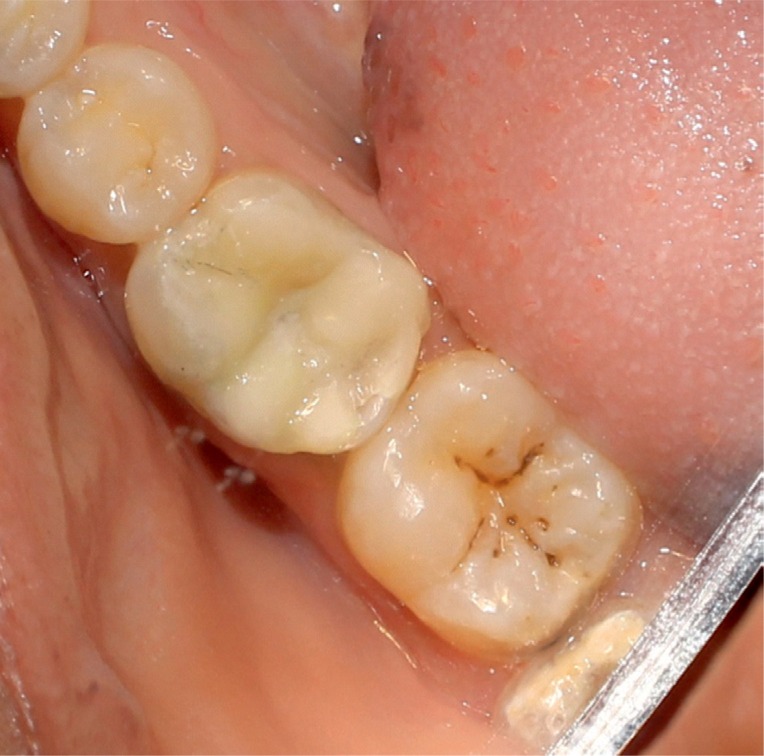

A 25 year old female patient presented to the Department of Conservative Dentistry and Endodontics with a chief complaint of pain in the region of the mandibular right first molar. She reported that an emergency access opening was performed one week prior for the same. Upon clinical examination, extensive destruction of the coronal tooth structure was noted (

Figure 1Preoperative photograph exhibiting extensive destruction of the coronal tooth structure.